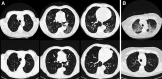

High Prevalence of Pulmonary Sequelae at 3 Months after Hospital Discharge in Mechanically Ventilated Survivors of COVID-19